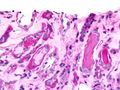

Micrograph showing myeloma cast nephropathy in a kidney biopsy. Hyaline casts are PAS positive (dark pink/red - right of image). Myelomatous casts are PAS negative (pale pink - left of image). PAS stain.

Atypical plasma cell infiltrate with both Russell (cytoplasmic) and Dutcher (nuclear) bodies (H&E, 50x).